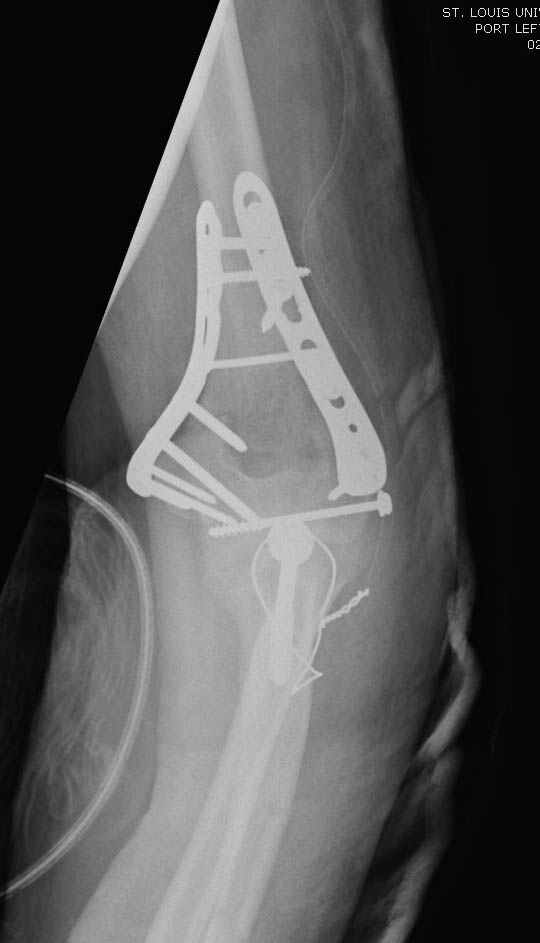

Примерный случай, только перелом был открытый, в задне-медиальной стороне рана около 2 см по характеру "изнутри кнаружи", неврологический статус со слабостью сгибания мизинца, также слабая абдукция и аддукция указательного пальца и сгибания в кисти.

Больному сделали обработку и наложили временный аппарат внешной фиксации плечо-предплечье.

На шестой день сделали открытую репозицию чрезлоктевым доступом двумя locking plate, локтевой нерв был ушибленным, после операции положительная динамика в Flexor Carpi Ulnaris. Фиксацию локтевого отростка произвели tension band technique с дополнительным шурупом.

Этапы операции на снимках....

Джолдас Кульджанов

Djoldas Kuldjanov, MD

Department of Orthopedic Surgery

St. Louis University Medical Center